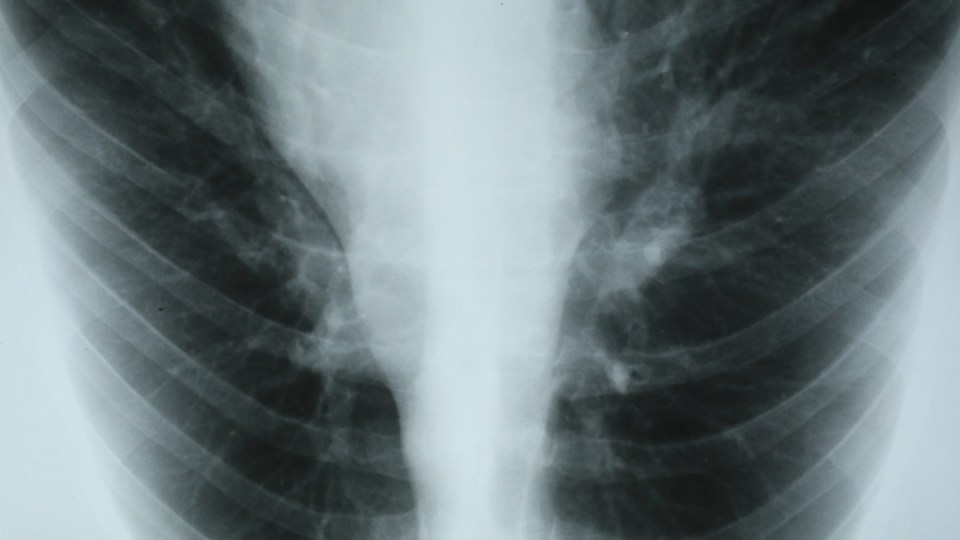

Australian researchers have identified unique molecular characteristics of an aggressive, hard-to-treat type of lung cancer known as adenocarcinoma that could help identify patients most likely to respond to immunotherapies.

Adenocarcinoma accounts for around 40 per cent of lung cancers and is often associated with a history of smoking, but is also the most commonly diagnosed lung cancer in non-smokers.

It occurs more frequently in females and in young people than other types of lung cancer.